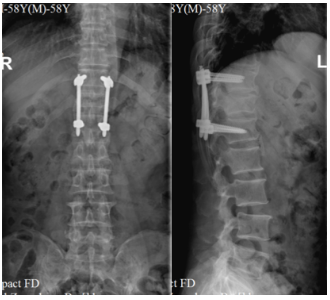

为了养家糊口,胡大叔已经在外打工多年。这天,胡大叔还是和往常一样来到工地,熟练地上到一个3米高的平台开始做活。可没做多久,胡大叔一个踉跄,不慎从平台跌落,臀部着地,重重摔在了地上,剧烈的疼痛让胡大叔忍不住惨叫起来。周围的工友急坏了,赶忙把胡大叔送到附近的南方医院增城分院急诊科就诊。检查发现胡大叔胸12椎体爆裂性骨折,遂转入骨科接受进一步治疗。术前影像学检查示胸12椎体爆裂骨折

术后X线复查椎弓根螺钉位置良好